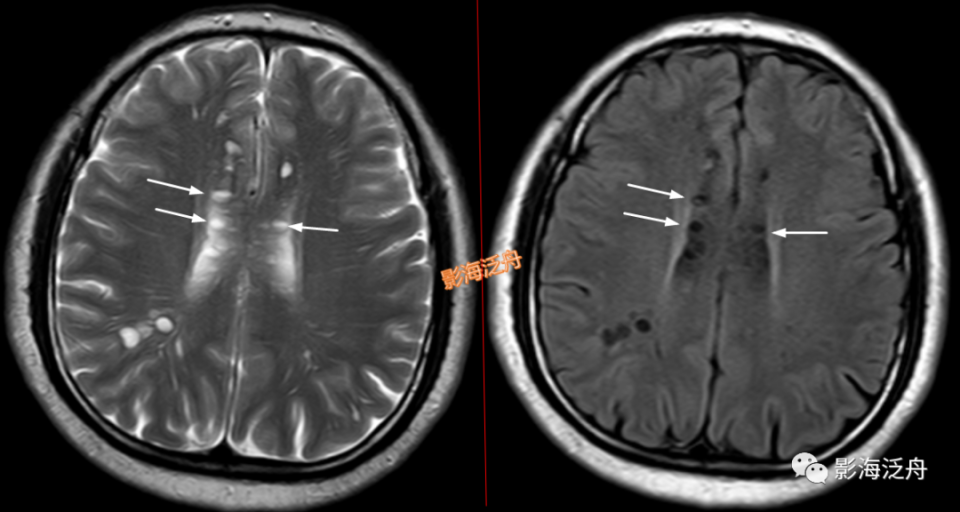

II型-大脑半球型:扩大VR腔隙呈对称性广泛分布于双侧半卵圆中心及皮层下白质区域(黄箭),少位于扣带回旁(白箭),部分呈类圆形(红箭头),部分呈裂隙样/线样(蓝箭头),注意绿箭头所指的VR腔隙边缘可见Flair高信号影,这种高信号可能是局部液体少量渗漏造成的。